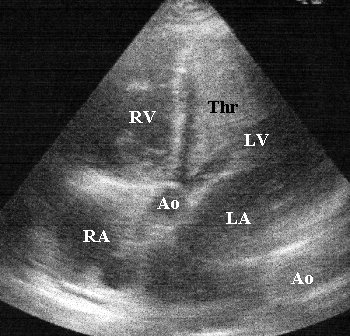

Echokardiographie

- Hypokinesie aller Herzwände

- Mitralinsuffizienz II°, Trikuspidalinsuffizienz

II°

- im linken Ventrikel stellt sich

ein die Kammer nahezu ausfüllender Thrombus dar, teilweise organisiert

(4x4cm) mit frei flottierendem Anteil (2x4cm), der Berührung mit der

Aortenklappe aufnimmt

- im rechten Ventrikel 2x2cm, organisierter

Thrombus im Bereich der Herzspitze